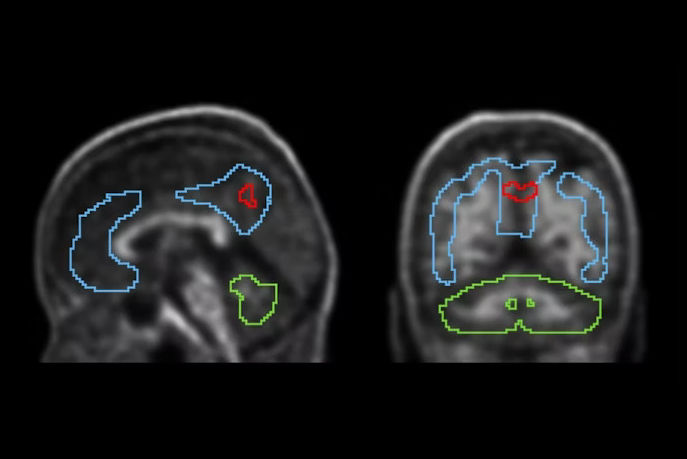

“Just as we're starting to tackle things like SUV values [standard uptake values] and trying to harmonize and standardize that from one system to another for diagnostic purposes, now we have this huge new challenge with theranostics where we now need to keep track in some way of the treatments that we're giving to patients and to try and quantify the responses to those treatments,” Siegel said.

Also, initial efforts are underway toward appropriate DICOM usage for nuclear medicine theranostics imaging and dosimetry data, and standardization of other metadata, such as radioactivity meter calibrations, PET and SPECT calibration, and imaging and dosimetry workflows, Siegel noted.